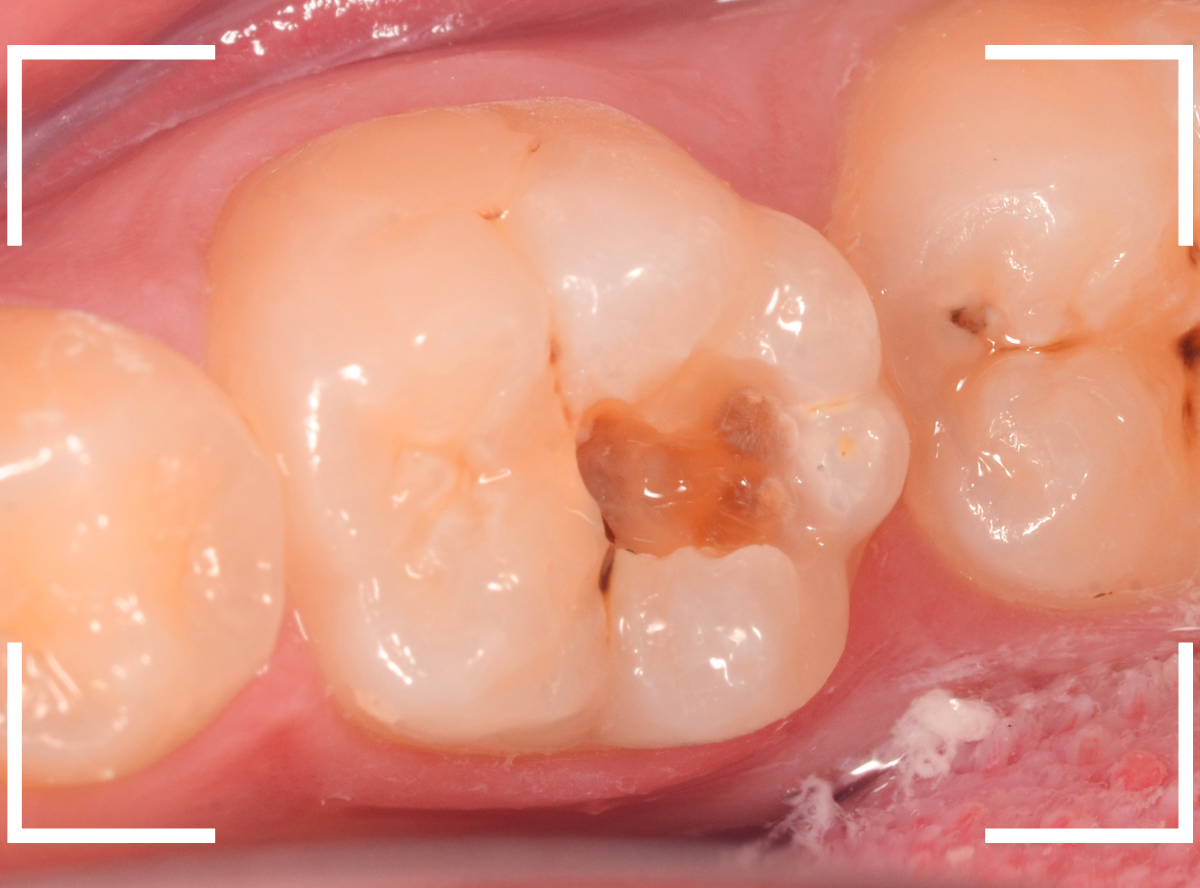

裂溝部分を少し削ると、中は虫歯で大きな空洞になっていました。

表面の虫歯を削って確認すると、中で虫歯が広がっているのが確認されました。

虫歯の部分を少しずつ削りながら、虫歯を確認します。

左側の歯はかなり虫歯が広がっているのがわかりますね。

典型的な、内部で広がる小窩裂溝う蝕です。

少し削ると、すぐに虫歯の部分が出てきました。

慎重に虫歯を削っていきます。